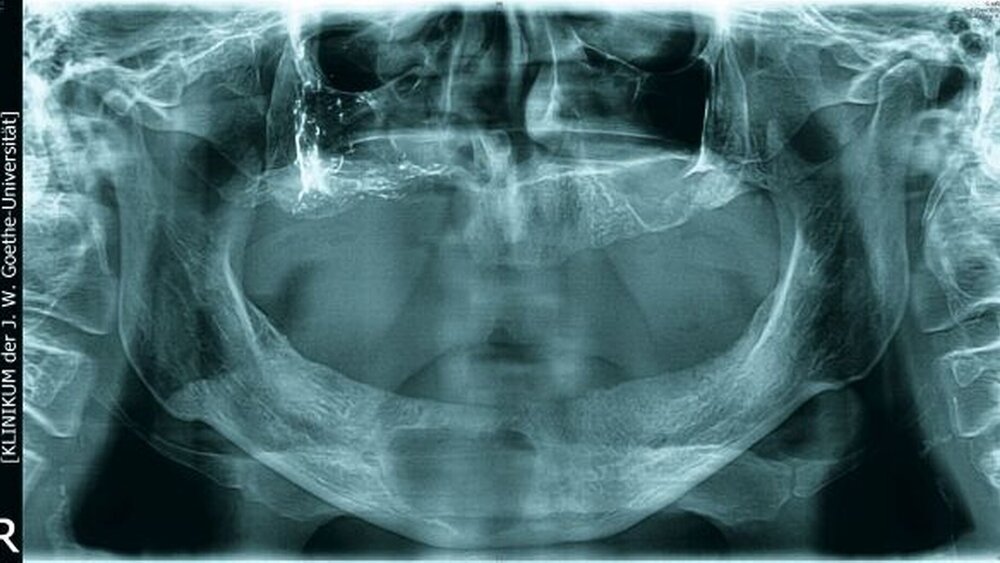

Bei der klinischen Inspektion imponierte ein desolates Gebiss bei starkem Knochenabbau und großflächigem Nekroseareal vestibulär im ersten Quadranten. Die Restbezahnung bestand aus den Zähnen 17, 15, 11 bis 24, 27 sowie 43 und 44. Alle Zähne wiesen Lockerungsgrad III auf. Neben einer spontanen Zahnfleischblutung konnte an mehreren Stellen eine putride Sekretion aus dem Parodontalspalt beobachtet werden. Des Weiteren wies der Patient einen enorm fauligen Foetor ex ore auf.

Die Computertomografie der Nasennebenhöhlen (NNH-CT) (nativ) zeigte dann das Ausmaß der knöchernen Destruktion. Neben der ausgedehnten generalisierten Nekrose des Oberkiefers konnte nebenbefundlich eine zystische Läsion im Bereich des Unterkiefers Regio 41 bis 45 diagnostiziert werden. Voraussichtlich ging diese vom Wurzelrest des Zahnes 41 aus. Weiterhin bestand eine totale Verschattung beider Sinus maxillaris und eine akzentuierte Lymphadenopathie in allen abgebildeten Leveln.